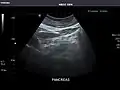

Pancreas: Visualized portions unremarkable.

Pancreas -